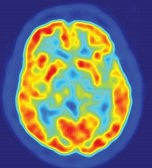

mapeo funcional computarizado del cerebro